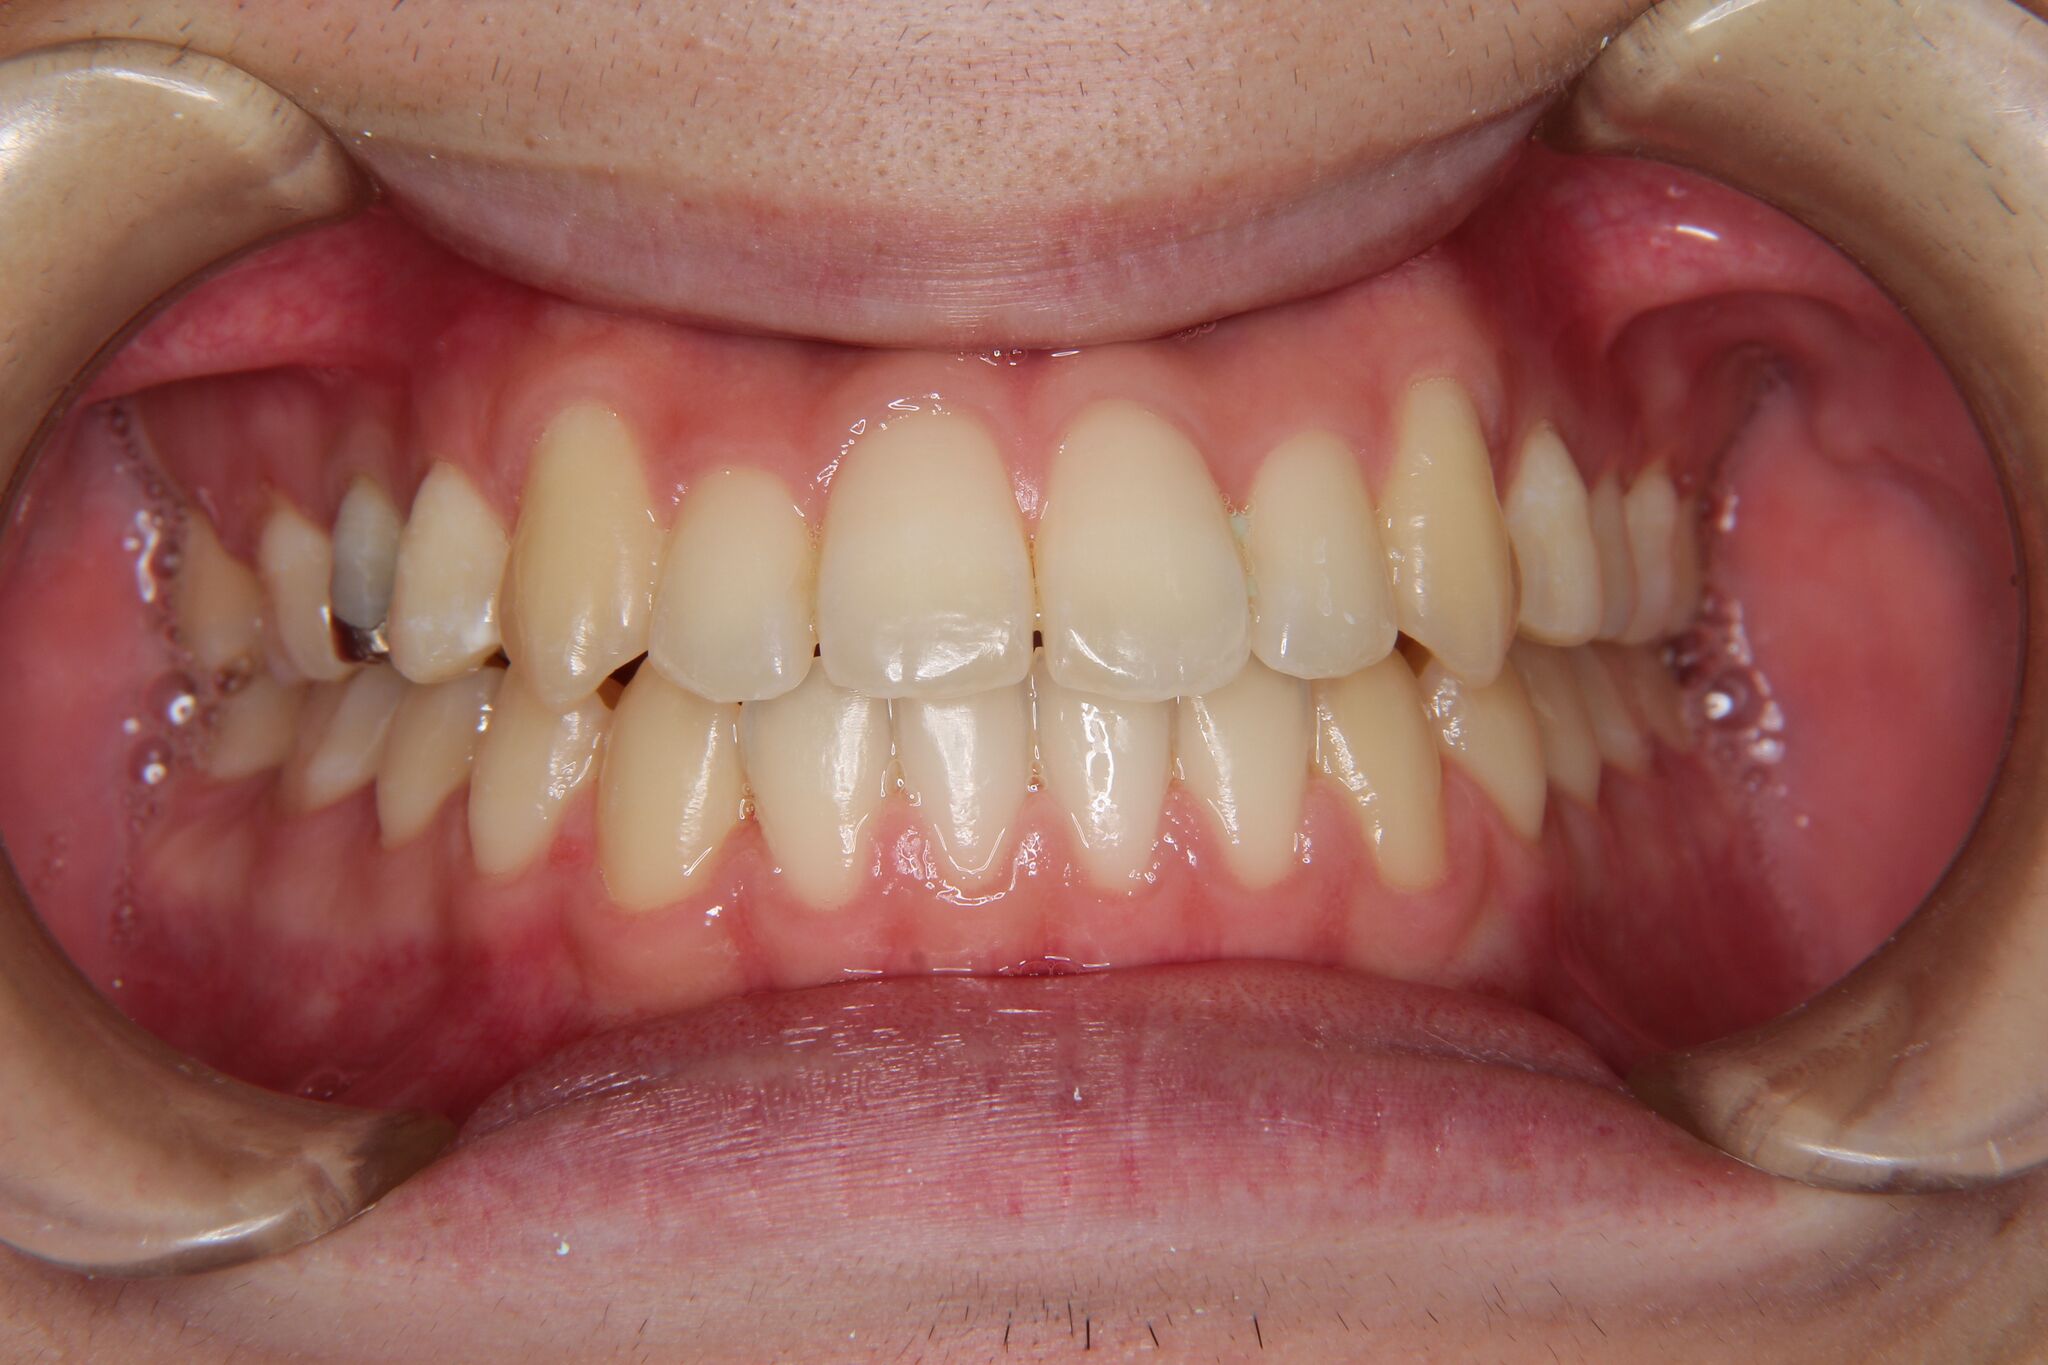

受け口

反対咬合(上顎前歯部叢生)

【患者】 10代 男性

【期間】 1年5カ月

- 治療前 治療後

非抜歯で治療を行いました。

- 上顎大臼歯部の遠心移動

- 下顎歯列全体のアップライティング